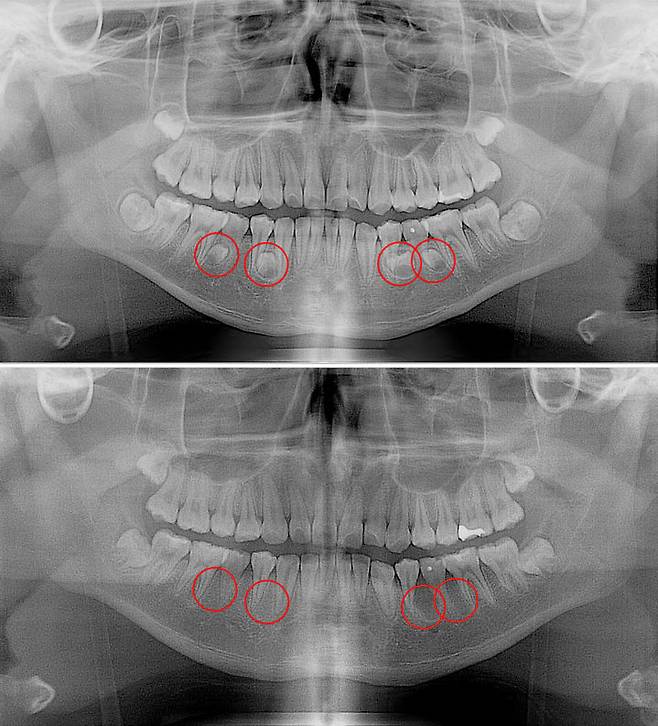

![[서울=뉴시스] 17일 의료계에 따르면 과잉치를 방치하면 치아의 정상적인 맹출(치아가 잇몸 속에서부터 잇몸을 뚫고 올라오는) 과정에 문제가 생길 수 있고, 추가적인 수술과 교정 치료가 필요할 수도 있다. (사진=고대안산병원 제공) 2025.04.17. photo@newsis.com *재판매 및 DB 금지](https://img4.daumcdn.net/thumb/R658x0.q70/?fname=https://t1.daumcdn.net/news/202504/18/newsis/20250418070106044cuem.jpg)

[서울=뉴시스]송종호 기자 = 20세 김호영(가명) 씨는 어린 시절부터 치아가 고르지 못하고 자주 잇몸이 붓는 문제가 있었지만 대수롭지 않게 생각해 왔다. 그는 시간이 지날수록 치아 배열이 점점 더 불규칙해져서 씹을 때도 어려움을 겪고 있다. 김 씨는 치과 엑스레이에서 과잉치가 원인이라는 사실을 알았다.

18일 의료계에 따르면 일반적으로 사람의 구강에는 28개의 영구치와 4개의 사랑니가 나와 총 32개의 치아가 자라게 돼았으나 이보다 더 많거나 불필요한 치아가 추가로 생기는 경우 과잉치라고 부른다.

과잉치를 방치하면 치아의 정상적인 맹출(치아가 잇몸 속에서부터 잇몸을 뚫고 올라오는) 과정에 문제가 생길 수 있고, 추가적인 수술과 교정 치료가 필요할 수도 있다.

과잉치가 발생하는 정확한 원인은 밝혀지지 않았다. 다만 부모나 형제에게 과잉치가 있으면 발생 확률이 높아지는 것으로 보고 있다. 대부분이 턱뼈 내에 매복돼 있기 때문에 당사자 또는 보호자가 미리 알기는 매우 어렵다. 파노라마 방사선 촬영과 근단 방사선 사진 촬영, 컴퓨터 단층(CT) 촬영 등을 통해서만 발견할 수 있다.